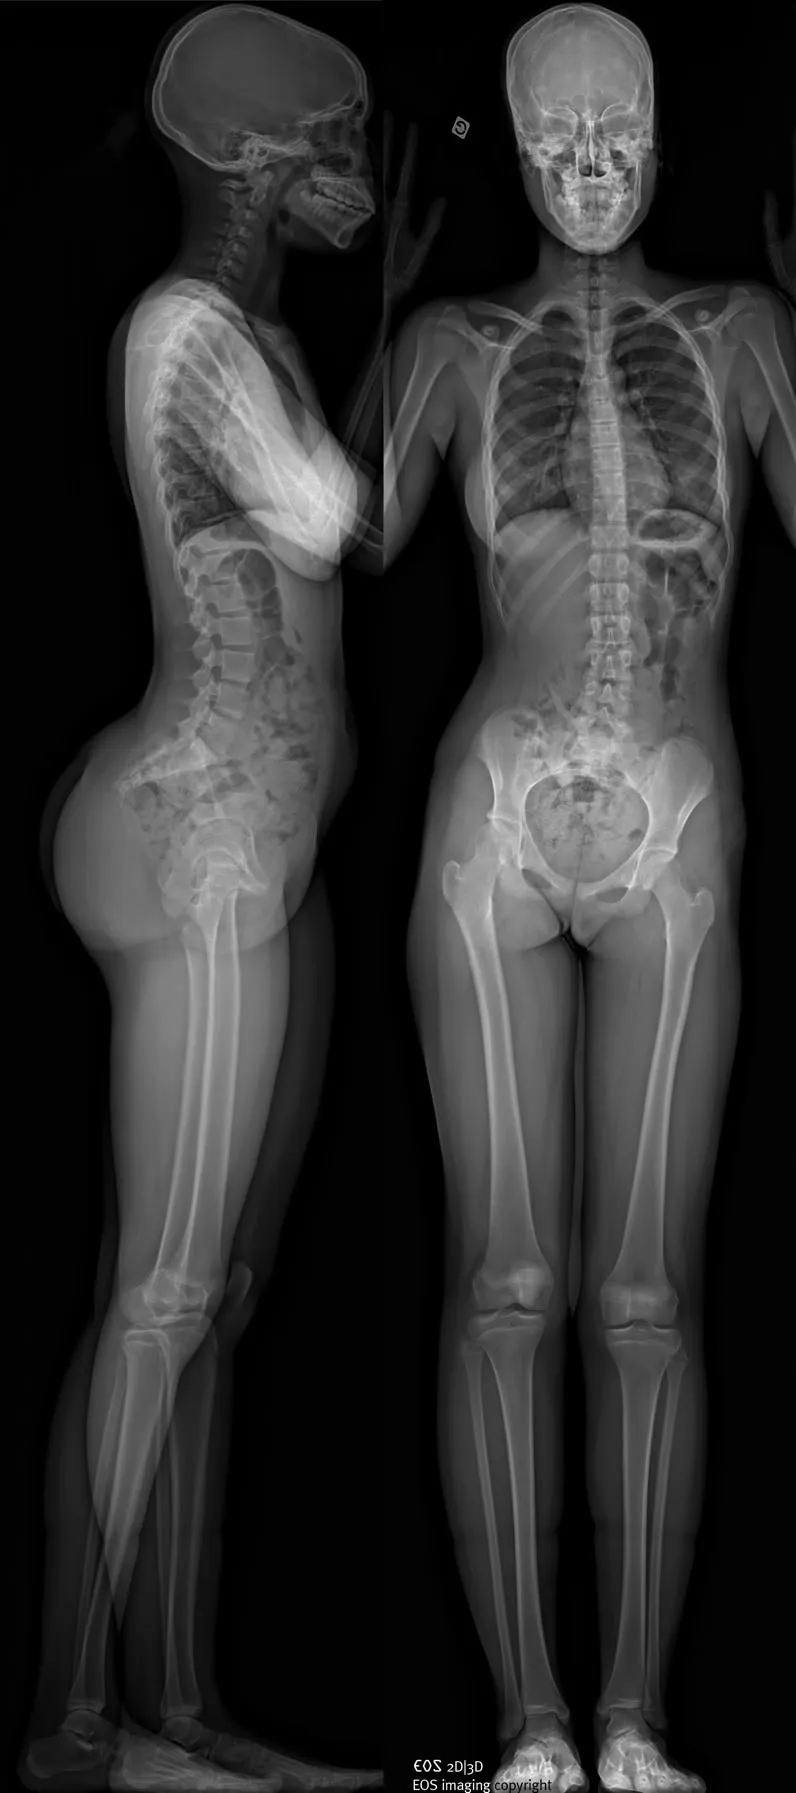

EOS réalise des radiographies du corps entier d’un patient en position debout, en une seule acquisition, sans assemblage d’images et sans distorsion verticale. Des clichés numériques de face et de profil, tout ou partie du corps, peuvent être obtenus simultanément, avec une qualité d’image exceptionnelle et sans aucun agrandissement pour une fiabilité parfaite des mesures.

Par un balayage de quelques secondes, une image de face et une de profil du corps entier en charge ou d’une zone anatomique choisie sont acquises simultanément. Un peu comme à la manière d’une photocopieuse, un très fin pinceau de rayons X balaye le corps du patient, de la tête aux pieds, simultanément de face et de profil.

Imagerie face/profil corps entier en charge

Non seulement l’examen est très peu irradiant, mais il est d’une exhaustivité que les examens conventionnels ne permettent pas d’atteindre. En effet l’acquisition se fait en charge (debout), de face et de profil, de façon parfaitement simultanée. Ces deux acquisitions peuvent être réalisées en charge mais aussi lors de manœuvres dynamiques. Cela permet une analyse statique et dynamique complète.

La technique même d’acquisition permet de réaliser des mesures précises contrairement aux radiographies conventionnelles.